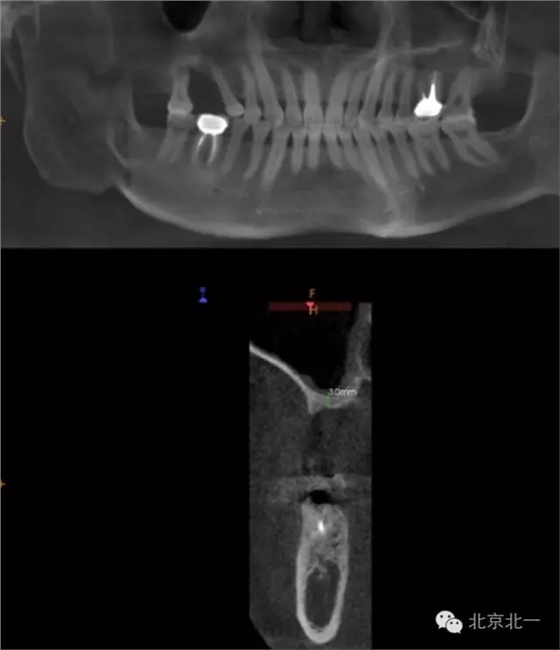

CBCT顯示,骨寬度可,骨高度不足,月3mm。頜間距離增大。

圖三:骨高度3mm.

圖十八:手術前CBCT